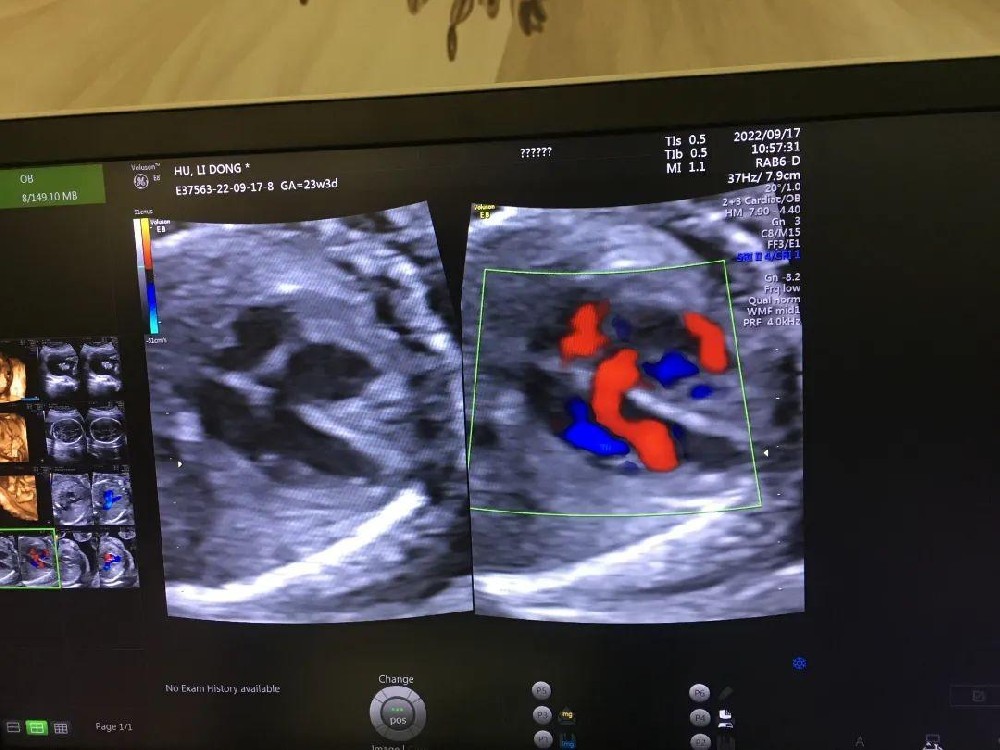

• 揪心!33岁妈妈怀孕23周在汉产检发现胎儿先天性心脏畸形

近日,一位33岁的高龄一胎妈妈,孕23周+时在湖北省武汉仁爱医院做常规四维彩超检查时,超声科检查出胎儿先天性心脏畸形。超声结果显示,胎儿头颅、颜面、胸部、腹部、脊柱、四肢等部位发育都没有明显异常,是一个非常活泼好动的宝宝,可唯独在心脏部位发现了结构异常。四维彩超图武汉仁爱医院超声影像科主任王娟根据胎儿心脏